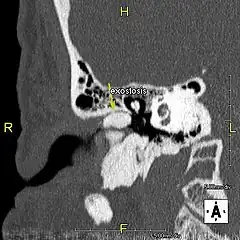

L'exostose du surfeur ou oreille de surfeur est une exostose, c'est-à-dire une croissance osseuse anormale, qui pousse vers l'intérieur du conduit auditif[1]. L'os entourant le conduit auditif réagit à l'agression thermique et mécanique de l'eau froide et de ses turbulences, par une nouvelle croissance osseuse qui a pour effet de resserrer le conduit auditif.

Du fait de la réduction du diamètre du conduit auditif, l'eau et le cérumen peuvent rester piégés entre la masse osseuse et le tympan et provoquer ainsi une infection comme une otite externe, particulièrement douloureuse.

Le contact de l’os avec le tympan peut provoquer des acouphènes[4]. Si rien n'est fait, les excroissances osseuses peuvent conduire à une obturation du conduit auditif et à une perte d'audition[1].